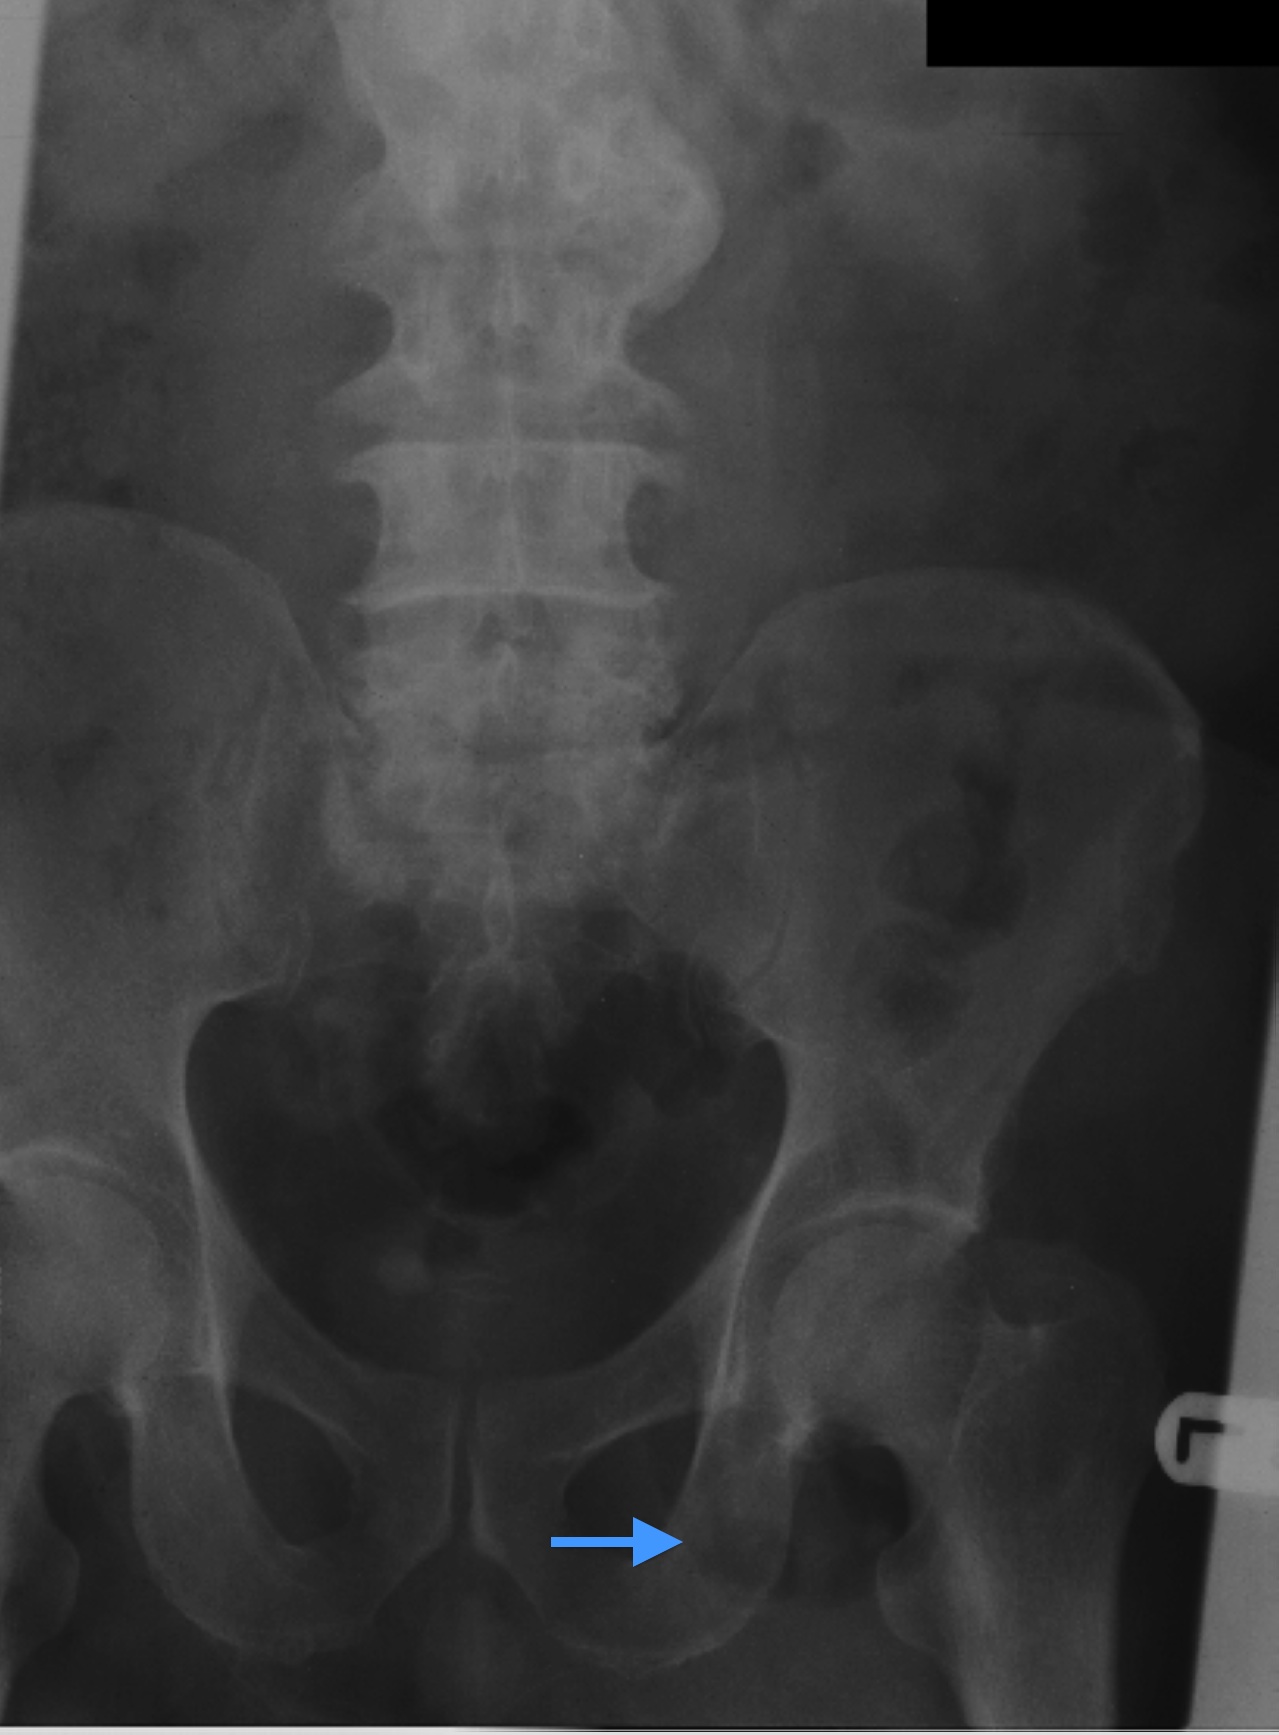

Small bowel obstruction is a common clinical presentation that presents a diagnostic conundrum. Over the last 2 decades, there has been a paradigm shift in the radiological investigation of small bowel obstruction (SBO) and in the indication for and timing of surgical intervention. Cross sectional imaging (predominantly computed tomography) has largely replaced the widespread use of radiographic small bowel follow-through studies as the imaging modality of choice for SBO. This article illustrates the current imaging modalities available for diagnosis of small bowel obstruction. (Full text available online at www.medpharm.tandfonline.com/ojfp) S Afr Fam Pract 2015; DOI: /10.1080/20786190.2014.977052